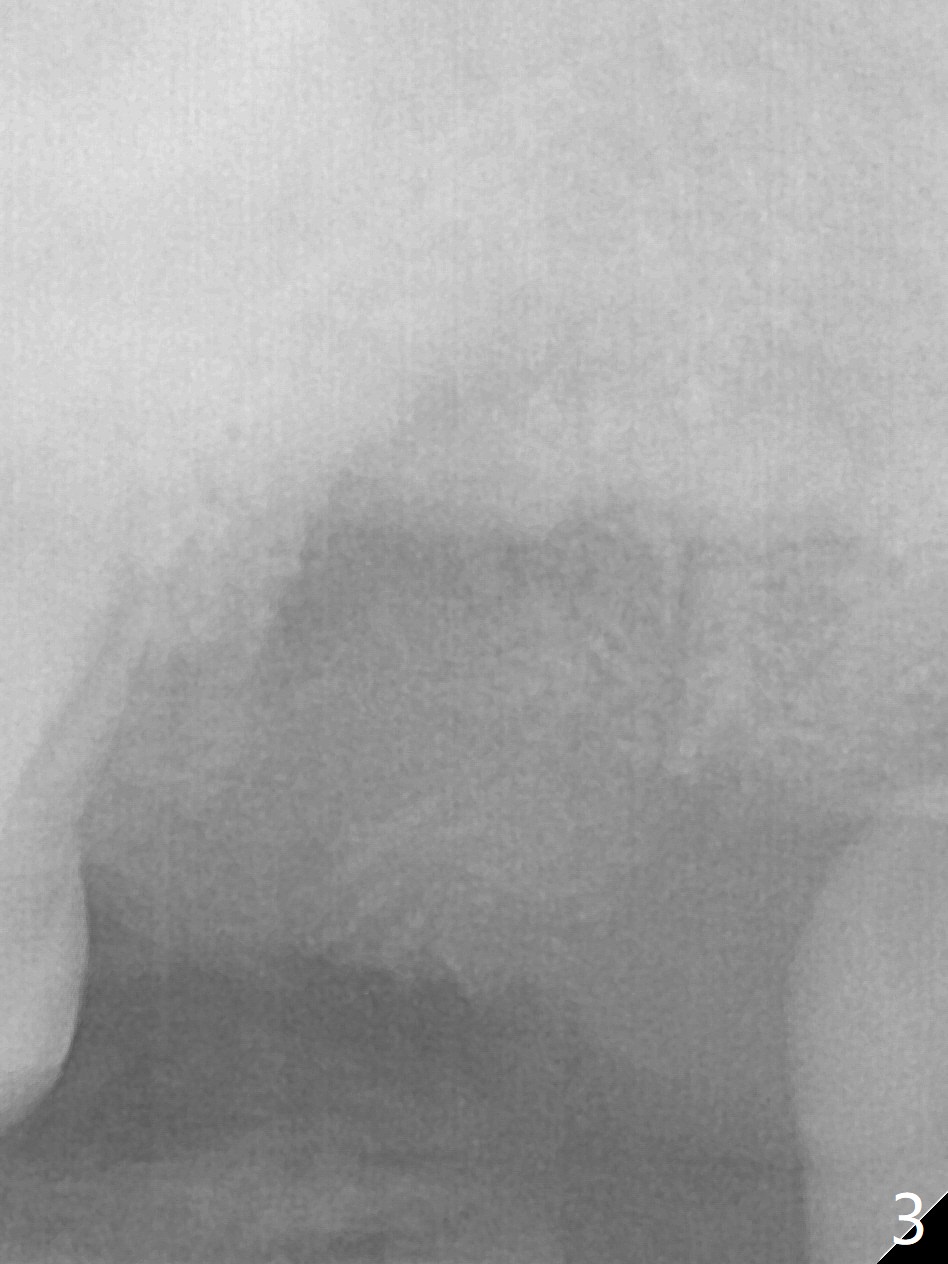

Large Upper 2nd Molar Socket After Vertical Root Split

A 45-year-old man with #4 crown fracture and C deciduous tooth returns to clinic with chief complaint of "chewing pain" UL. It seems that the distal marginal ridge of the tooth #15 has simple oblique subgingival fracture. With one carpule of Xylocaine, the distal portion cannot be removed because of pain. X-ray reveals vertical root fracture (Fig.1,2). With additional carpules of Septocaine and Marcaine, the tooth is removed. The socket is large with abundant granulation tissue. After debridement, a large amount of Vanilla graft and a whole piece of Osteogen plug is placed for socket preservation (Fig.3).